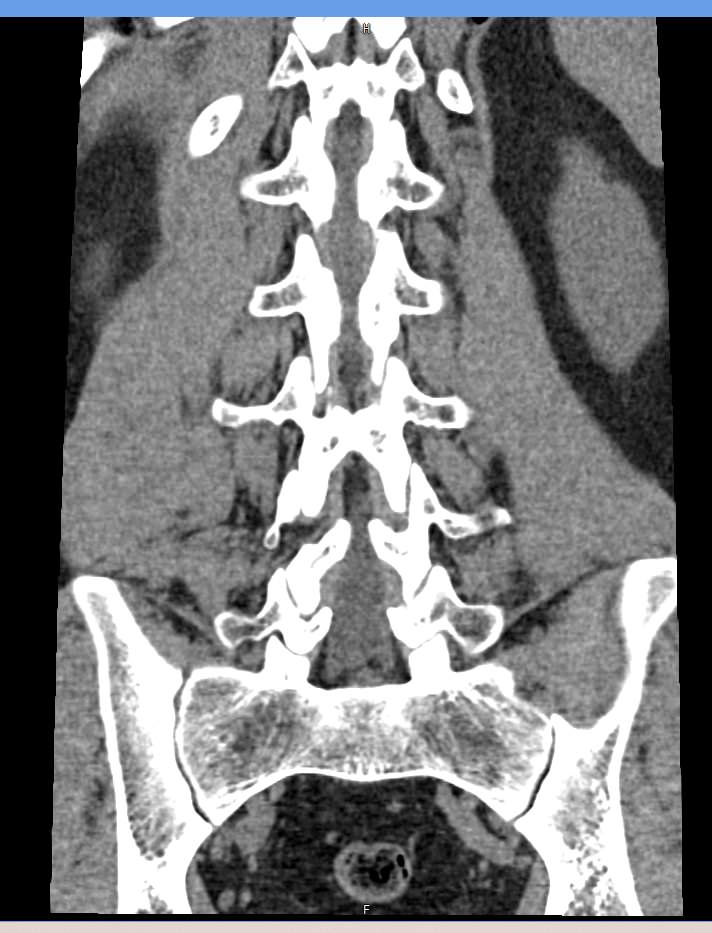

Мультиспиральная компьютерная томография является наиболее точным и информативным методом диагностики различных заболеваний позвоночника и, в частности, пояснично-крестцового отдела. Сканирование проводится при помощи рентгеновского излучения, в результате чего получают серию послойных изображений пояснично-крестцового отдела позвоночника.

В медицинских центрах «Доступная медицина» обследование пояснично-крестцового отдела позвоночника осуществляется на современных мультиспиральных компьютерных томографах последнего поколения TOSHIBA AQUILION в модификациях, позволяющих выполнять одномоментно 64 и 128 срезов анатомической зоны для получения снимков высокого разрешения. Послойное сканирование исследуемой области проводится с минимальной толщиной среза от 0,5 мм, что обеспечивает получение изображений органов в мельчайших подробностях.

Инновационные компьютерные приложения позволяют построить 3D-модель исследуемого органа, обеспечивая детальную визуализацию строения внутренних структур позвонков, хрящевых элементов, кровеносных сосудов и окружающих тканей.

- изгиб позвоночного столба (поясничный лордоз нормальный, усилен или сглажен);

- не смещены ли позвонки относительно друг друга;

- нет ли признаков костной деструкции, остеопороза;

- нормальная ли высота тел позвонков;

- нет ли грыж (протрузий, экструзий), и если есть – где они находятся, на сколько миллиметров выступают в просвет позвоночного канала, какие анатомические структуры сдавливают;

- патологические изгибы позвоночника.